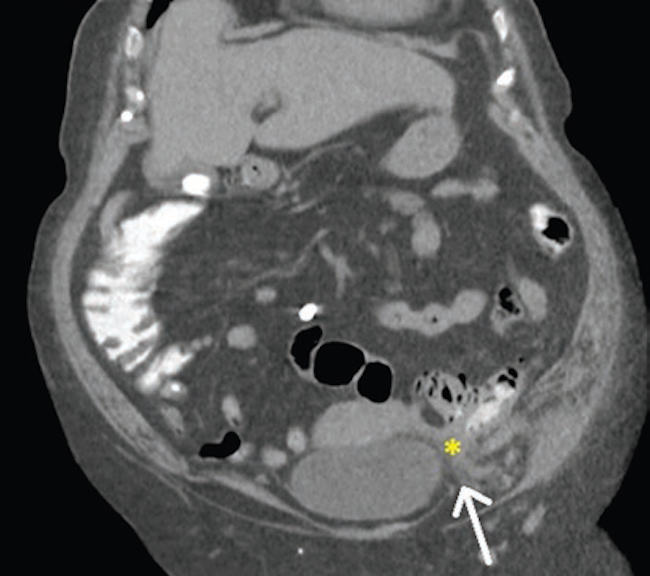

Dados los hallazgos ecográficos, se realizó una tomografía computada abdominal y pélvica, en la que se observaron una solución de continuidad de 22 mm en el flanco izquierdo (Fig. 1) y una imagen ovalada ligeramente edematizada (Fig. 2). En la cavidad pelviana se observó una imagen líquida de aspecto quístico de 91 × 87 × 81 mm, dependiente de anexo derecho (Fig. 3). Durante su internación, la paciente persistió con dolor a nivel referido y fue llevada a laparotomía exploratoria, en la que se halló un tumor abscedado sobre la aponeurosis del músculo oblicuo izquierdo, del que se tomaron muestras para anatomía patológica, y se drenó y corrigió la solución de continuidad en el acto quirúrgico. Se amplió el estudio microscópico con marcadores tumorales CA 125 y CA 19-9, que fueron positivos para metástasis de carcinoma primario de ovario (Fig. 4). Actualmente, la paciente está en manejo oncológico.